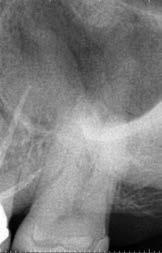

1. a-n. ábrák: Preoperatív CBCT-felvétel a bal alsó 6-os (3.6) fogról. Az axialis (a), coronalis (b) és sagittalis (c) nézeteken a mezialis és distalis gyökerek apicalis harmada körül sugáráteresztő zóna és ép buccalis corticalis csont látható. Egy olyan sablont terveztünk, amely jelezte a csontablak határait az apicalis terület pontos elérése érdekében (d). A mikrosebészeti bevatkozás során a sablont a helyére illesztettük (e), a csontablak határait megjelöltük (f) egy Piezotome CUBE LED kézi-darabba fogott fűrésszel, majd kivágtuk és eltávolítottuk (g és h) az apicalis területhez történő hozzáférés, illetve a mezialis és distalis gyökerek rezekciójának, retrográd preparációjának és retrográd gyökértömésének elvégzése érdekében (i). Végezetül a csontablakot visszaillesztettük és kollagén szivaccsal stabilizáltuk (j). A műtét után közvetlenül készített röntgenfelvétel a 3.6-os fogról (k). A kétéves kontroll során készített CBCT-felvétel: axialis (l), coronalis (m) és sagittalis (n) nézetek.

Egy 63 éves páciens korábban már kezelt bal alsó első nagyőrlőfogából (3.6) eredő mérsékelt fájdalom miatt kereste fel rendelőnket. A kórtörténetében panasza szempontjából releváns információ nem szerepelt. Az elkészült CBCT-felvételen a korábbi kezelések során észre nem vett, jelenleg feltáratlan meziobuccalis csatornát, valamint a mezialis és distalis gyökerek körül kialakult periapicalis elváltozást, és ezt a léziót borító intakt buccalis corticalis csontlemezt láttunk.

Klinikai vizsgálat során vertikális kopogtatási érzékenységet jelzett. A fog körül mérhető szondázási mélység és a fogmobilitás fiziológiás volt. A CBCT-felvételen nem észleltünk a csontos regeneráció megindulására utaló jeleket (1. a–c. ábrák). A korábban gyökérkezelt, gyökértömött és revideált 3.6-os fog esetében az alábbi diagnózis került felállításra: periodontitis periapicalis symptomatica. A panaszokat okozó fog további ellátása során navigált endodonciai mikrosebészetet kívántunk alkalmazni. Az alsó állcsontról intraorális szkent (TRIOS, 3Shape) készítettünk, és a felszíni topográfiát tartalmazó STL fájlt, valamint a CBCT-felvétel készítése során nyert DICOM fájlokat a Blue Sky Bio szoftver segítségével egyesítettük. A sebészi sablon megtervezésére az így kapott háromdimenziós képet használtuk. A sablon kialakítása során arra törekedtünk, hogy a sablon egyértelműen meghatározza a gyökércsúcsi terület eléréséhez szükséges csontablak határait (1. d. ábra)